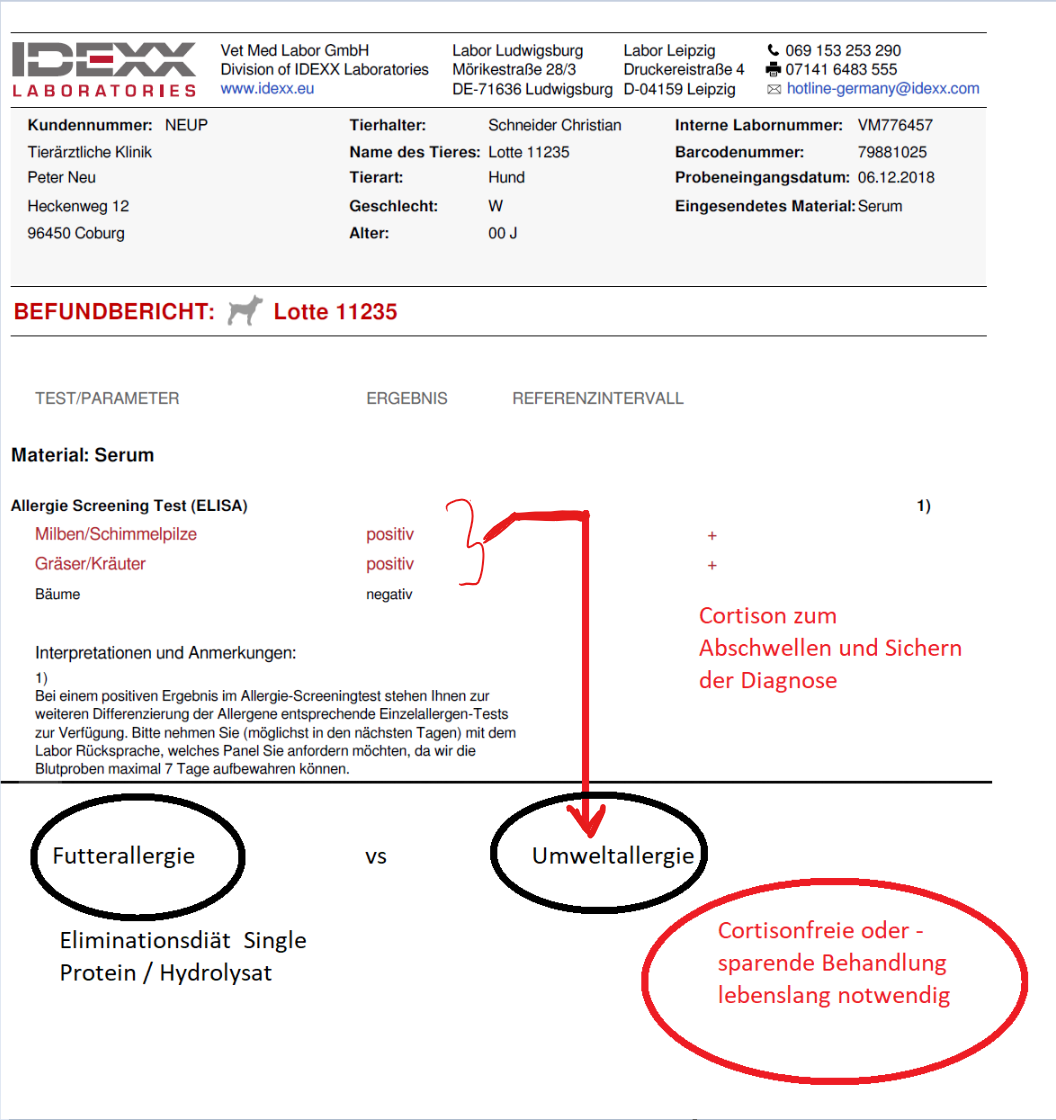

Hier kann man zwei verschiedene Gründe für das Fortbestehen einer Gehörgangsuntersuchung vermuten. Links ist der IgE Nachweis für Milben und Schimmelpilze positiv. Es könnte sich also um einen Hund mit Atopie(Neurodermitis/Allergie) handeln. Bei dem Patienten rechts sind die Schilddrüsenwerte sehr niedrig. Wenn auch das TSH nicht erhöht ist, was für eine echtes Schilddrüsenproblem sprechen würde, sollte man das Krankheitsbild der “subklinischen Hypothyreose” in Erwägung ziehen. Beide Patienten müssen sehr genau in diese Richtungen untersucht werden um die Verdachtsmomente zu bestätigen bzw auszuschliessen. Man kann auch eine diagnostische Behandlung durchführen um sich der Sache zu vergewissern.

Stellt sich bei der Blutuntersuchung heraus, dass IgE Antikörper im Screening vorhanden sind, ist eine Allergie als Ursache für die immer wiederkommenden Ohrentzündungen sehr wahrscheinlich. Der Hund leidet dann an einer sogenannten Atopie, die der menschlichen Neurodermitis sehr ähnlich ist. Das muss sicher erkannt werden. Ich persönlich setze dann ein kurz wirksames Cortisonpräparat ein um die Diagnose abzusichern und das Ohr erst mal abzuschwellen. Ziel ist es aber unbedingt, von diesem Cortison möglichst schnell wieder loszukommen, auch wenn es am Anfang fantastisch wirkt.